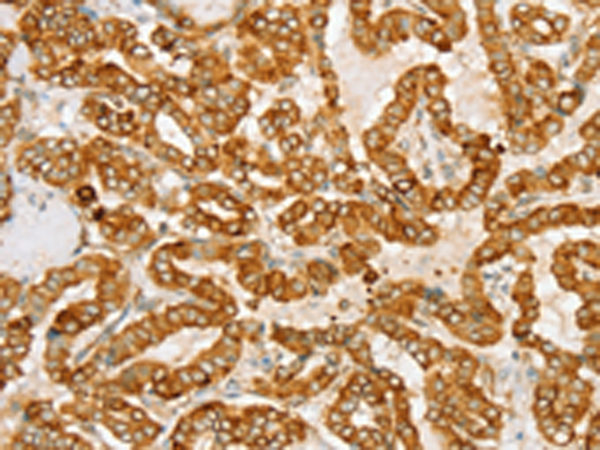

分类: 科研抗体货号: P01689别名: CATX-8; RAB11C应用: IHC反应种属: Human, Mouse